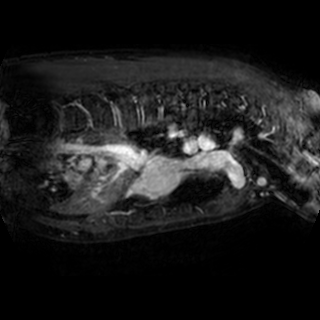

The integration of deep learning systems into healthcare has been hindered by the resource-intensive process of data annotation and the inability of these systems to generalize to different data distributions. Foundation models, which are models pre-trained on large datasets, have emerged as a solution to reduce reliance on annotated data and enhance model generalizability and robustness. DINOv2 is an open-source foundation model pre-trained with self-supervised learning on 142 million curated natural images that exhibits promising capabilities across various vision tasks. Nevertheless, a critical question remains unanswered regarding DINOv2's adaptability to radiological imaging, and whether its features are sufficiently general to benefit radiology image analysis. Therefore, this study comprehensively evaluates DINOv2 for radiology, conducting over 100 experiments across diverse modalities (X-ray, CT, and MRI). To measure the effectiveness and generalizability of DINOv2's feature representations, we analyze the model across medical image analysis tasks including disease classification and organ segmentation on both 2D and 3D images, and under different settings like kNN, few-shot learning, linear-probing, end-to-end fine-tuning, and parameter-efficient fine-tuning. Comparative analyses with established supervised, self-supervised, and weakly-supervised models reveal DINOv2's superior performance and cross-task generalizability. The findings contribute insights to potential avenues for optimizing pre-training strategies for medical imaging and enhancing the broader understanding of DINOv2's role in bridging the gap between natural and radiological image analysis. Our code is available at https://github.com/MohammedSB/DINOv2ForRadiology